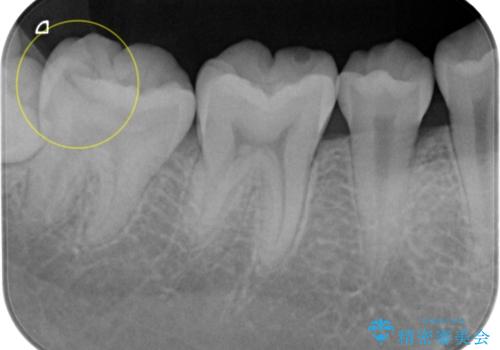

- 夜間の歯ぎしりを指摘されたことでナイトガード作成を希望して来院された患者様です。

厚いナイトガードでかみ合わせを微調整していきます。

全ての歯が均等に噛み合うよう調整することで噛む力を分散させ、一本の歯に噛む力が集中しないようにします。